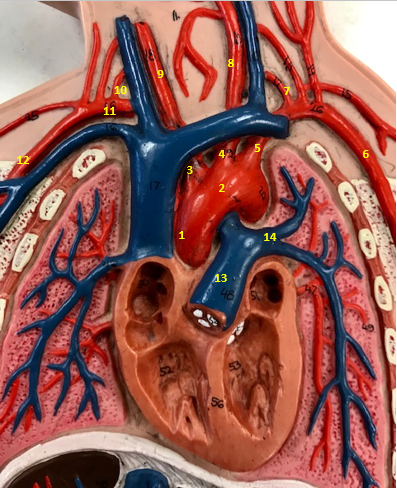

Aorta

Name #2

Brings blood out of left ventricle

Function of aorta

Brachiocephalic artery

Name #3

Supplies oxygenated blood to right arm shoulder neck and head

Function of brachiocephalic artery

Left common carotid artery

Name #4

Supplies oxygenated blood to left neck and head

Function of left common carotid artery

Left subclavian artery

Name #5

Supplies oxygenated blood to left arm shoulder

Function of left subclavian artery

Left axillery artery

Name #6

supplies blood to left armpit and upper limb

Function left axillary artery (6)

Left vertebral artery

Name #7

Supplies blood to brain and spinal cord

Function of left vertebral artery (7)

Left common carotid artery

Name #8

Supplies blood to left neck and head

Function of left common carotid artery (8)

Right common carotid artery

Name #9

Supplies oxygenated blood to right neck and head

Function of right common carotid artery (9)

Right vertebral artery

Name #10

Supplies blood to brain and spinal cord

Function of right vertebral artery (10)

Right subclavian artery

Name #11

Supplies blood to right arm and shoulder

Function of right subclavian artery

Right axillery artery

Name #12

Supplies blood to right armpit and upper limb

Function of right axillery artery (12)

Pulmonary trunk

Name #13

Bring blood out of right ventricle to lungs

Function of pulmonary trunk (13)

Left pulmonary artery

Name #14

Bring blood to left lung

Function of left pulmonary artery (14)